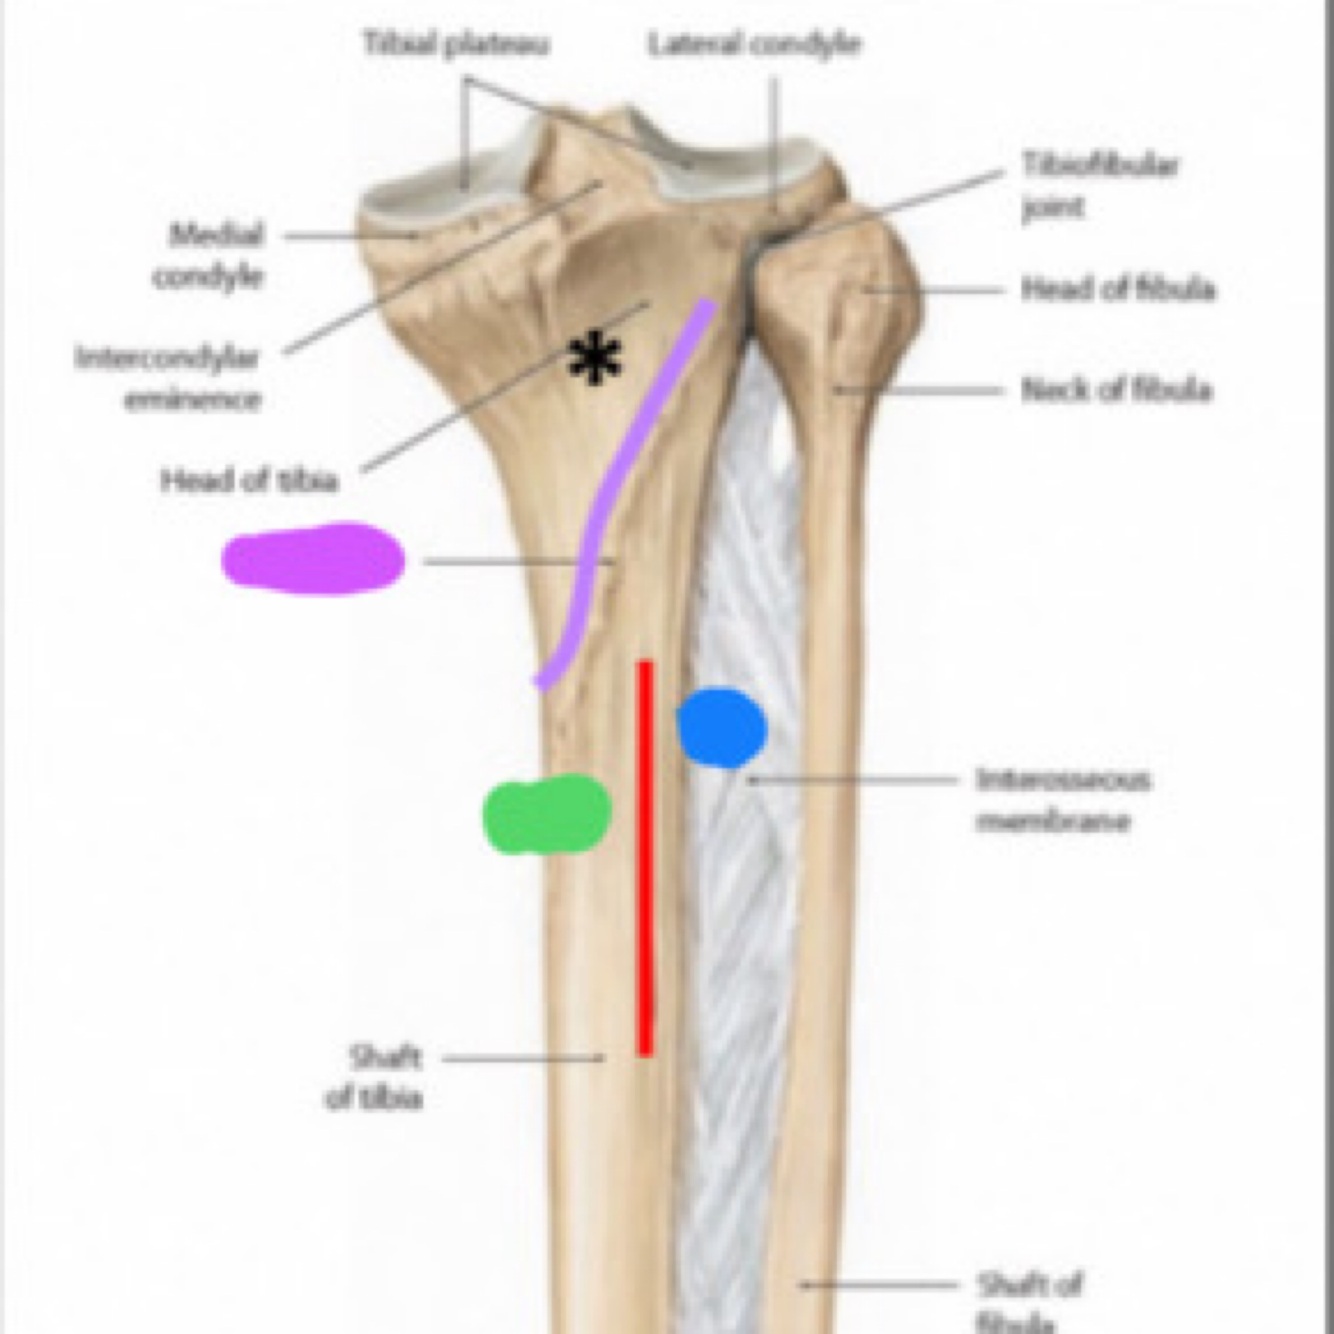

Quel est la structure que l’astérix pointe. Ya til une insertion musculaire a cet endroit? Laquelle?

La surface triangulaire du muscle poplité qui donne insertion du muscle poplité

La ________(rouge) sépare la diaphyse de la face postérieure du tibia pour 2 structures (bleu et vert).

Rouge: crête verticale

Vert: muscle long fléchisseur des orteils

Bleu: muscle tibial postérieur